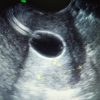

末年初,万象将更新,超声科迎来朝气蓬勃的景象。为了提升我院超声科的技术水平,为了支持医院的工作开拓社区业务,方阅读更多